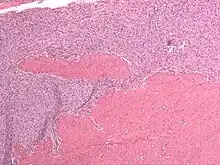

Endometrial stromal sarcoma (low-grade)

Low-grade endometrial stromal sarcoma consists of cells resembling normal proliferative phase endometrium, but with infiltration or vascular invasion. These behave less[3] aggressively, sometimes metastasizing, with cancer stage the best predictor of survival. The cells express estrogen/progesterone-receptors.

Microscopy

- Monotonous ovoid cells to spindly cells with minimal cytoplasm.

- Prominent arterioles. Angiolymphatic invasion common.

- Up to 10-15 mitotic figures per 10 HPF in most active areas.

- Tongue-like infiltration between muscle bundles of myometrium.

- May exhibit myxoid, epithelioid and fibrous change.

- May have foam cells or hyalinization in the stroma.